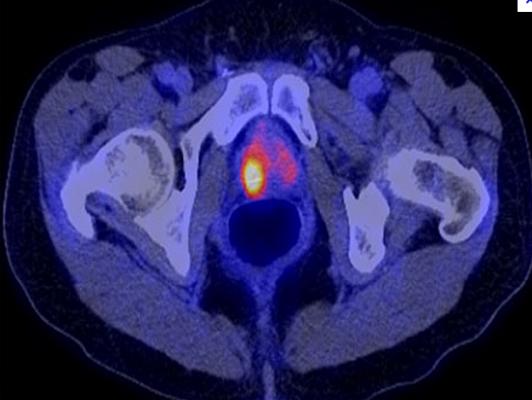

September 14, 2012 — The U.S. Food and Drug Administration (FDA) has approved the production and use of Choline C-11 injection, a positron emission tomography (PET) imaging agent used to help detect recurrent prostate cancer. Choline C-11 injection is administered intravenously to produce an image that helps to locate specific body sites for follow-up tissue sampling and testing in men with recurrent prostate cancer.

PET imaging with Choline C-11 injection is performed in patients whose blood prostate specific antigen (PSA) levels are increasing after earlier treatment for prostate cancer. An elevated PSA result suggests that prostate cancer may have returned, even though conventional imaging tests, such as computed tomography (CT), have not shown any signs of cancer. PET imaging is not a replacement for tissue sampling and testing.

The safety and effectiveness of Choline C-11 injection were verified by a systematic review of published study reports. Four independent studies examined a total of 98 patients with elevated blood PSA levels but no sign of recurrent prostate cancer on conventional imaging. After PET imaging with Choline C-11, the patients underwent tissue sampling of the abnormalities detected on the PET scans.

In each of the four studies, at least half the patients who had abnormalities detected on PET scans also had recurrent prostate cancer confirmed by tissue sampling of the abnormal areas. PET scan errors also were reported. Depending on the study, falsely positive PET scans were observed in 15 percent to 47 percent of the patients. These findings underscore the need for confirmatory tissue sampling of abnormalities detected with Choline C-11 injection PET scans. Aside from an uncommon, mild skin reaction at the injection site, no side effects to Choline C-11 injection were reported.